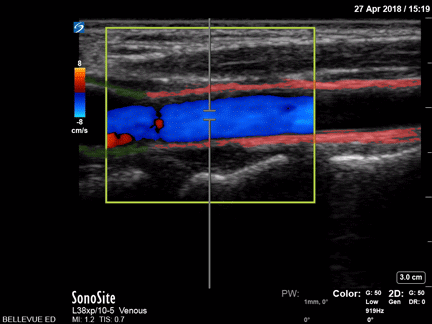

Long Axis of Common Carotid Artery Red: Common carotid artery, Green: Carotid bulb Images: Dr. Lindsay Davis, Dr. Hannah Kopinski. Image Editing: Michael Amador and Dr. Matthew Riscinti